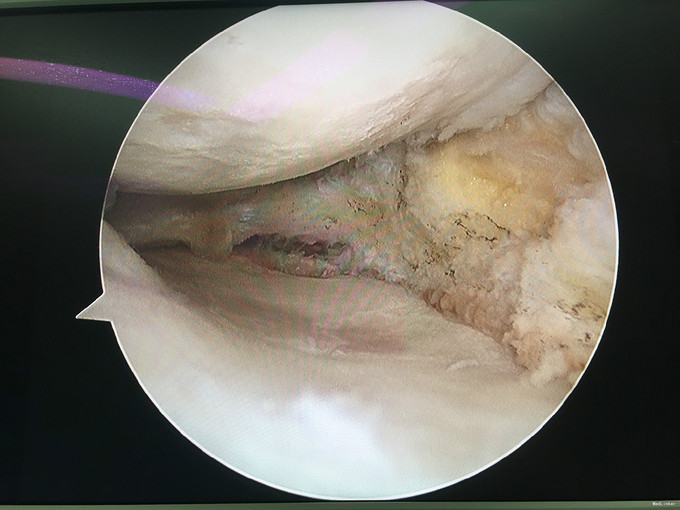

诊断:类风湿性关节炎 治疗:右膝关节镜下清理

随访:患者术后早期术膝肿胀消除明显,活动度较术前明显改善。患者继续至风湿免疫科行内科治疗。 讨论:对风湿性疾病的局部症状治疗,关节镜手术治疗不失为一实用而又有效的治疗方法。